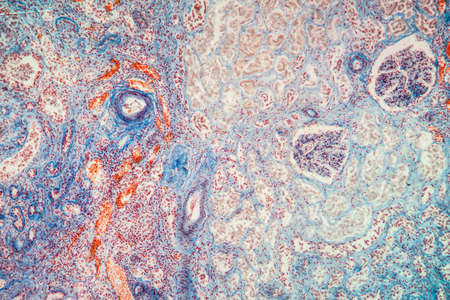

Breast cancer of the woman diseased tissue 100x